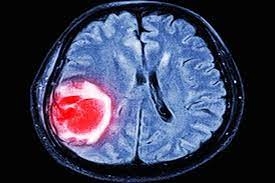

O Glioblastoma Multiforme (GBM) é o tipo mais comum e agressivo de tumor cerebral maligno que se desenvolve a partir das células gliais do cérebro. Ele é caracterizado por múltiplos focos de tumor no cérebro e crescer rapidamente, infiltrando os tecidos circundantes. A causa exata do GBM é desconhecida, mas acredita-se que seja causada por uma combinação de fatores genéticos e ambientais.

Geralmente, afeta adultos entre 45 e 70 anos, sendo mais comum em homens do que em mulheres. As consequências do glioblastoma multiforme podem causar danos significativos e comprometer funções vitais dependendo da localização do tumor no cérebro.

O diagnóstico de GBM geralmente é feito com base em uma combinação de histórico médico, exame físico, exames de imagem e testes de laboratório. Os exames de imagem que podem ser usados ??para diagnosticar GBM incluem tomografia computadorizada (TC), ressonância magnética (MRI) e tomografia por emissão de pósitrons (PET). Os testes de laboratório que podem ser usados ??para diagnosticar GBM incluem um exame de sangue e um exame de líquido cefalorraquidiano (LCR).